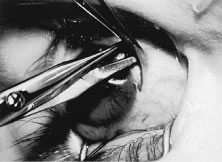

RESECTION PROCEDURE: LIMBAL APPROACH

Incision is made into the conjunctiva at the limbus (Fig. 64).

Fig. 64. After the stay sutures have been placed, the conjunctiva is tented with a forceps. An incision is made at the limbus.

The assistant elevates the conjunctiva while the surgeon uses a Stevens' hook to elevate the rectus muscle (Fig. 65). A Jameson muscle hook is passed under the muscle tendon in a plane that is tangential to the scleral surface, about 3 mm behind the tented rectus muscle insertion. Figure 66 shows the rectus muscle on the Jameson hook.

Fig. 65. The rectus muscle insertion is secured with a Jameson hook by passing the hook tangential to the globe.

Fig. 66. The conjunctiva is held up with a forceps while the surgeon holds the rectus muscle tissue on the Jameson hook. The tip of the hook is exposed and is covered by intermuscular septa and anterior Tenon's capsule.